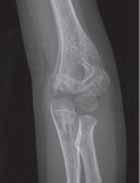

Rozpoznanie

Objawy złamania to silny ból uniemożliwiający stanie i chodzenie, zniekształcenie obrysów stawu kolanowego przez krwiak i różnego stopnia przemieszczenie nasady kości piszczelowej. Należy dokładnie zbadać stan ukrwienia i unaczynienia kończyny pod kątem objawów uszkodzenia tętnicy podkolanowej i nerwu strzałkowego. Trzeba ocenić bolesność uciskową oraz napięcie w przedziałach powięziowych podudzia: przednim, bocznym, tylnym powierzchownym i tylnym głębokim. U pacjentów z podejrzeniem wzmożonego ciśnienia wewnątrzprzedziałowego należy wielokrotnie powtarzać badanie ukrwienia i unerwienia kończyny, a w razie zaistnienia wskazań wykonać bezpośredni pomiar ciśnienia w przedziałach. Powinno się zawsze podejrzewać możliwość uszkodzeń więzadłowych współistniejących ze złamaniem. Badania obrazowe to RTG w pozycji AP, bocznej i skośnej. Wykonanie badania TK może być konieczne w celu pełnej oceny rozległości

złamania. W przypadku podejrzenia uszkodzenia tętnicy podkolanowej należy wykonać angio-TK lub arteriografię.

Leczenie

Leczenie złamania bliższej nasady piszczeli w przypadku uszkodzenia typu 1 i 2 według Saltera i Harrisa leczymy nieoperacyjnie. Należy wykonać zamkniętą repozycję i unieruchomić w opatrunku gipsowym udowym w zgięciu kolana 30–60°, zapewniającym najlepszą stabilność odłamów. Okres unieruchomienia wynosi od 6 do 7 tygodni. Po tym czasie usuwamy gips i zaczynamy ćwiczenia zwiększające zakres ruchomości stawu kolanowego oraz wzmacniające siłę mięśnia czworogłowego. Ważne jest, by prowadzić częste kontrole stanu ukrwienia i unaczynienia oraz kontrole radiologiczne w celu wykrycia ewentualnych przemieszczeń odłamów. Złamania pierwotnie niestabilne lub wtórnie przemieszczone wymagają zamkniętej repozycji stabilizacji drutami K. Typ 3 i 4

Złamania rzepki i podudzia

złamania według Saltera i Harrisa wymaga leczenia operacyjnego w postaci otwartej repozycji i stabilizacji śrubami. Należy unikać krzyżowania metalu zespalającego z chrząstką wzrostową. Kończynę zgiętą w kolanie do 30° unieruchamia się w gipsie udowym na okres 6–8 tygodni. Po tym czasie rozpoczynamy ćwiczenia czynne poprawiające zakres ruchomości kończyny.